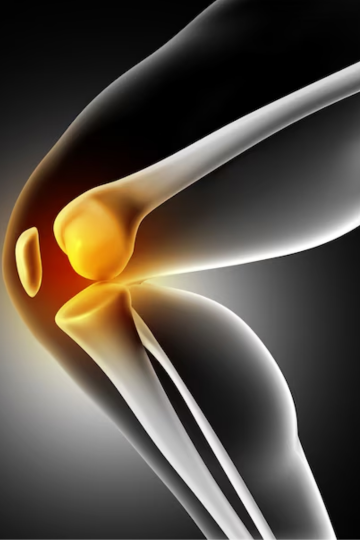

Knee Arthroscopy

Knee arthroscopy is a surgical technique of orthopedic surgery in which examination and treatment of the interior of the knee joint are performed with an arthroscope. In this process, a small fiber-optic camera also referred to as an arthroscope is used and the incisions are very small to enable visualization inside the knee joint. This enables the surgeon to not only see the cartilage, ligaments and other tissues inside the knee but also to reach them easily. Besides for diagnosing and examining a joint, arthroscopy can be applied for a number of corrective operations, for instance, to suture torn ligaments, to take out the damaged cartilage, or to wash out the joint. This method, otherwise, is considered less painful and the recovery time is comparatively shorter than the open surgeries.

Knee arthroscopy is one of the trends in modern orthopedic surgery that allows for the assessment and treatment of the internal knee space. Dr Abhijit Tayade is known as the top orthopedic doctor in Delhi to guide you on knee arthroscopy and clear all your doubts. Well, in this process, through small incisions, arthroscopy is performed, and a small fibre optic camera is inserted to view and repair the cartilage, ligaments, and other tissues in the knee. His expertise makes him the best knee replacement surgeon in South Delhi.

With this minimally invasive technique, the best orthopedic surgeon in New Delhi, Dr. Abhijit Tayade, is able to diagnose the problem and treat it through surgery, which may involve reattachment of a torn ligament, cartilage removal, or washing out of a joint with less pain than in open surgery and a faster rate of recovery.